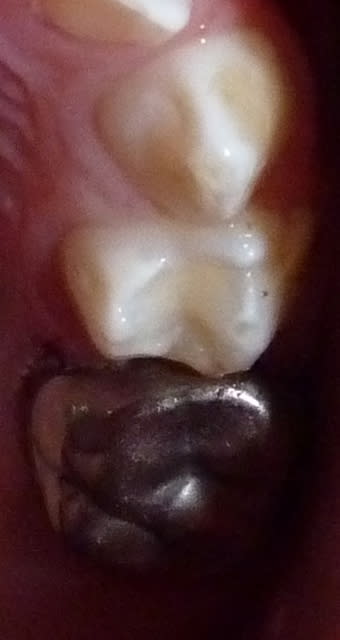

Dans le cas ci-dessous, la 1ère photo est prise après début d’éviction carieuse : sur la 4, on voit déjà la pulpe par transparence. Les tubuli dentinaires d'une dent temporaire sont beaucoup plus larges et nombreux que sur une dent permanente. Ainsi, une carie dentinaire infecte très rapidement la pulpe camérale. Faire une restauration sans pulpotomie dans ce cas aurait probablement abouti à une nécrose à moyen terme.